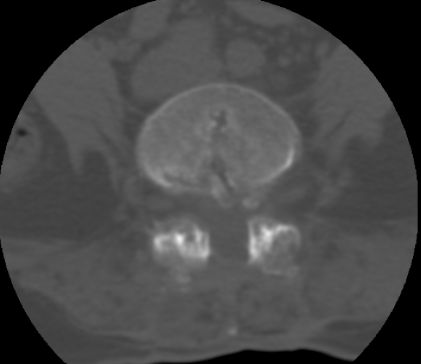

以下是引用余辉在2007-9-4 21:00:00的发言:[br]椎体棘突有点异常(像是被切割了),不知有否手术史,如椎体融合术等。单纯的退行性变可以出现椎间隙变窄,但同时一般会出现椎体上下缘的硬化增生,且椎体间完全融合的机率更小,本例椎体完全融合且椎体上下皮质缘破坏掉了,如果没有手术史,就应该考虑椎间盘炎性病变了,且椎体棘突及棘间韧带的变化也并不是不支持这个,多数小关节也融合了,且其形态也容易让人联想到如强脊炎及类风关等病变。[br][br][本贴已被 余辉 于 2007-9-4 21:03:55 修改过]

以下是引用chry3在2007-9-4 20:42:00的发言:[br]椎间盘病史?是什么样的病史,无双下肢放射痛,那就不是椎间盘突出了。是感染、什么性质的?[br]从图象看椎间隙消失,椎间盘组织未见,锥体滑脱是因为椎间盘溶解造成的[br]l4、5椎体骨质结构未见异常,l5上缘是l4的长期压迫所致[br]还是考虑椎间盘感染,结核。[br]